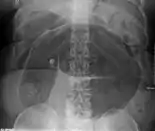

After taking a thorough history, the diagnosis of colonic volvulus is usually easily included in the differential diagnosis. Abdominal plain x-rays are commonly confirmatory for a volvulus, especially if a "bent inner tube" sign or a "coffee bean" sign are seen. These refer to the shape of the air-filled closed loop of colon which forms the volvulus. Should the diagnosis be in doubt, a barium enema may be used to demonstrate a "bird's beak" at the point where the segment of proximal bowel and distal bowel rotate to form the volvulus.